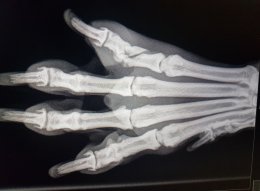

Röntgenfoto’s

worden gemaakt met behulp van röntgenstralen. Deze gaan dwars door

het lichaam heen en worden dan opgevangen op een plaat die gevoelig

is voor deze stralen. De

informatie die op deze plaat

staan wordt door een speciaal apparaat uitgelezen en omgezet naar een

digitaal beeld. De dierenarts kan hierna de röntgenfoto beoordelen.